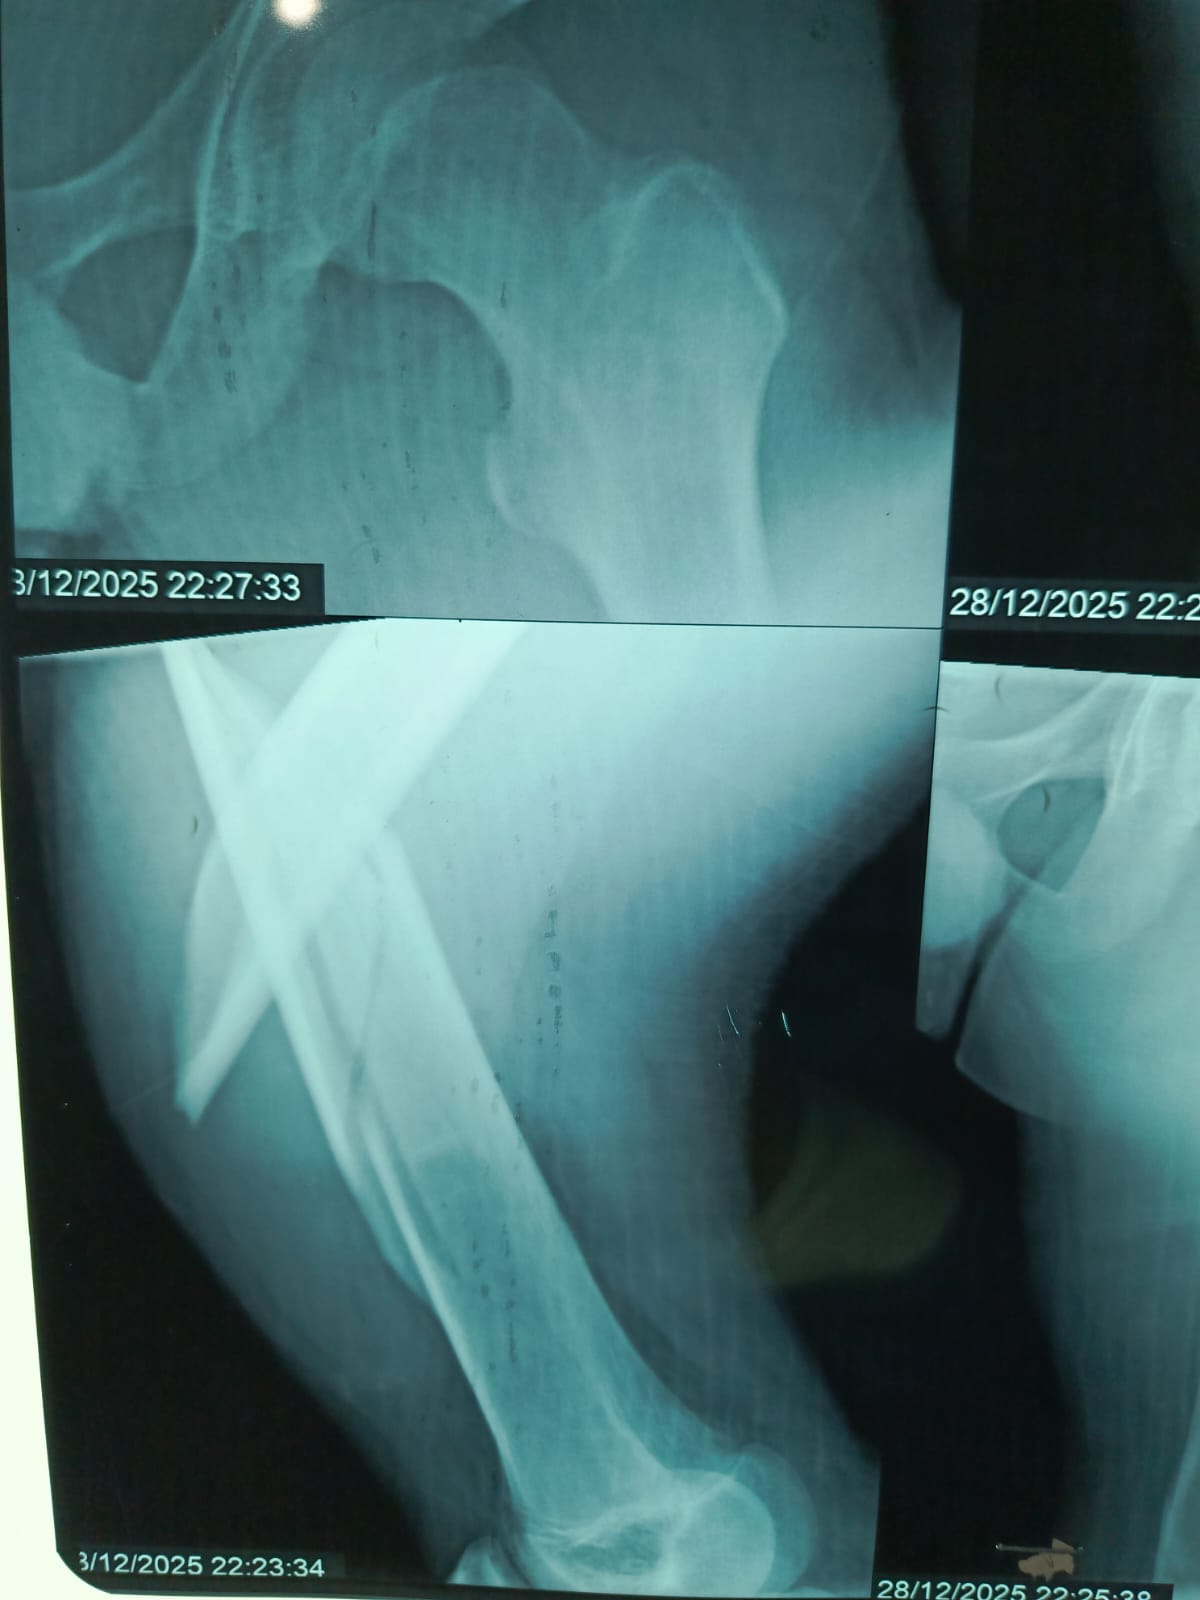

مستشفى مغاغة العام ينقذ شاباً مصاباً بكسر معقد في الفخذ بعد حادث مروري

حقق الفريق الطبي بمستشفى مغاغة العام بمحافظة المنيا إنجازاً طبياً جديداً، بعدما نجح في إنقاذ شاب يبلغ من العمر 16 عاماً، وصل إلى المستشفى إثر حادث مروري عنيف أسفر عن كسر مفتت متعدد المواضع بعظمة الفخذ الأيسر، في تدخل عكس سرعة الاستجابة وكفاءة التعامل مع الحالات الطارئة.

تدخل جراحي سريع بتقنيات حديثة

استنفرت أطقم الطوارئ جهودها فور وصول المصاب، واتخذ الفريق الطبي قراراً عاجلاً بإجراء جراحة المسمار النخاعي التشابكي دون فتح موضع الكسر، ما ساهم في تقليل المضاعفات وتسريع وتيرة العلاج.

أنهى الفريق الجراحي العملية خلال ساعتين ونصف، وخرج الشاب من غرفة العمليات في حالة مستقرة، وفق معايير طبية حديثة تعتمد على التدخل محدود الجروح، وتقليل فقدان الدم، وخفض فرص العدوى، مع تسريع معدلات التئام العظام مقارنة بالأساليب التقليدية.